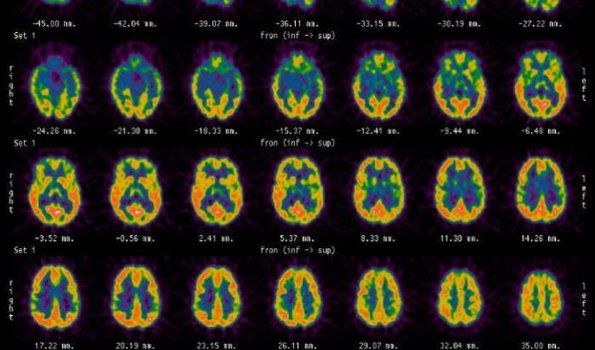

El neurólogo Facundo Manes, autor de Usar el cerebro (Planeta) y director del Instituto de Neurología Cognitiva (Ineco) y el Instituto de Neurociencias de la Fundación Favaloro, enumeró 10 actividades para ejercitar nuestra mente.